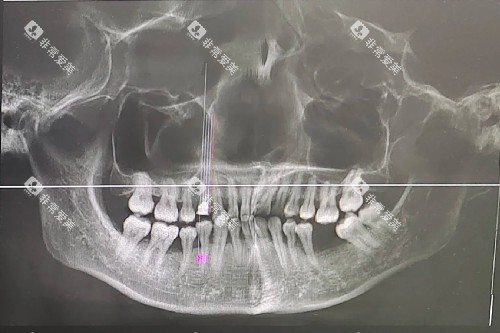

种植牙是目前修复缺失牙比较理想的方式,它能较好地改善牙齿的功能和美观。

张家口市第一医院口腔科的种牙收费受到多种因素的影响。

患者自身情况

如果患者的牙槽骨条件不佳,在种牙前需要进行骨增量手术等额外治疗,这也会增加种牙的费用,一般骨增量手术的费用在3000 - 8000元不等。

张家口市第一医院口腔科的根管治疗收费与牙齿的位置和根管数量有关。